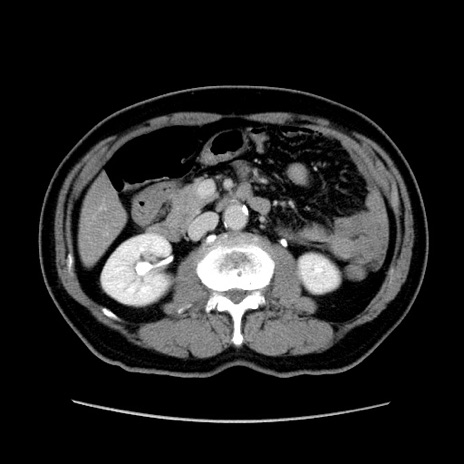

症例34(横断像)

【症例】60歳代 男性

【主訴】右鼠径部膨隆

【現病歴】1年程前より右鼠径部膨隆あり。自己にて還納可能だったため放置していた。3時間前より右鼠径部の脱出を認め、還納困難となり受診。

【既往歴】高血圧

【身体所見】右鼠径部に小児頭大の膨隆あり。弾性硬であり、用手還納は困難。左鼠径部にも膨隆を認める。脱出はなし。

【データ】WBC 15500、CRP 測定なし